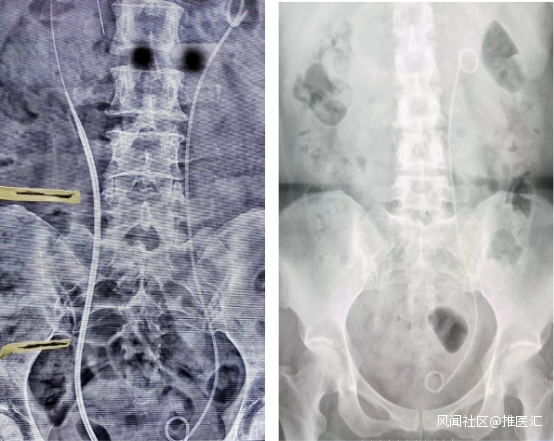

經傅強主任診斷為宮頸癌晚期合併輸尿管狹窄,考慮到患者目前病情,傅強主任醫療團隊組織了針對該患者的病例討論,在與患者進行了充分溝通後,逐定於17日進行手術。術中醫生們無懼射線,反覆確認導管位置,進行了永久螺旋雙覆膜鎳鈦合金Allium支架置入。該病例是六院首例Allium支架輸尿管置入術,術後患者的輸尿管被擴張,順利排尿,快速為患者解除了燃眉之急。患者恢復良好,複查KUB片支架位置良好。輸尿管引流通暢,無明顯腰痛等不適症狀。